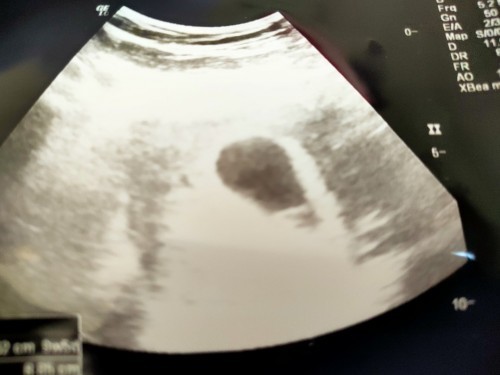

วันนี้หมอนัด หมอซาวด์ท้องให้ แต่ยังไม่เห็นตัวน้อง ตอนนี้อายุครรภ์ 8สัปดาห์ 2วันคะ เลยทำให้ใจแม่ไม่ดี แต่ครรภ์ปกติดีคะ เห็นแต่ถุงตั้งครรภ์ #ท้องแรกคะ #ขอบคุณล่วงหน้านะคะ #ขอคำแนะนำหน่อยค่ะ

บ้านนี้ซาวด์ครั้งแรกน่าจะ8วีคเหมือนกันเห็นแต่ถุงตั้งครรภ์แม่กังวลเปนเดือนกว่าหมอจะนัดอีกที พอหมอนัดซาวอีกทีน้อง14วีคแล้วเปนตัวครบเลยตอนนี้16วีค4วัน แล้วคะ ใจเย็นนะคะคุนแม่ถ้าไม่มีอาการปวดท้องมีเลือดออก ตอนนี้ก้อบำรุงต่อไปคะ สู้ๆนะคะขอให้เจอน้อง